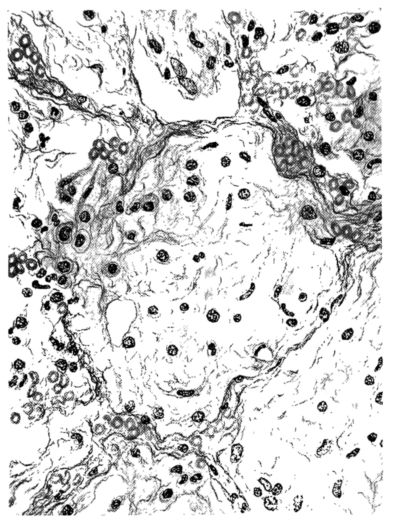

FIG. III. AUTOPSY NO. 90. DRAWING FROM A LESION OF THE TRACHEA (SOMEWHAT OLDER THAN THAT ILLUSTRATED IN FIGURE II). THE MUCOSA IS ENTIRELY LACKING. CONGESTION AND EDEMA ARE THE STRIKING FEATURES IN THE SUBMUCOSA. THE NECROTIZING PROCESS HAS EXTENDED INTO THE MUCUS GLANDS. THIS IS SHOWN IN THE LOWER PICTURE.

The changes are less marked, perhaps, in the trachea than in its finer ramifications. The mucosa is constantly more or less destroyed and large areas, usually focal, are entirely devoid of their epithelial covering. This is replaced by a sparse exudate, composed largely of red blood cells, mucus, a small amount of fibrin, and nuclear fragments (Fig. II). It may dip into the submucosa for a short distance, but usually these indentures are associated with the ducts of the mucous glands into which the inflammatory reaction extends. A more striking feature than the exudate, however, is the edema and the congestion of the submucosa. The loose areolar tissue of the submucosa is spread widely apart, and throughout it distended blood vessels are very conspicuous. Occasionally such a vessel is broken and actual hemorrhage appears in the submucosa. Occasionally, too, the inflammation extends down the duct to the mucous gland itself, and here, also, aplastic inflammatory reaction is evident, inasmuch as the acini now stain intensely red with the cells undifferentiated from each other and specked here and there by broken remains of the dead nuclei (Fig. III). After the disease has continued for a short period, even at the end of five or six days, some regeneration of the epithelial lining may be seen (3) (Fig. IV). But despite this, the acute picture persists, and there goes on, side by side, an attempted repair characterized by epithelial regeneration and the same evidence of acute change. Since the lesion is essentially a superficial one, scars or contractures of any extent are not encountered in the trachea, even in examples of the disease that have ended fatally only after many weeks.[4]